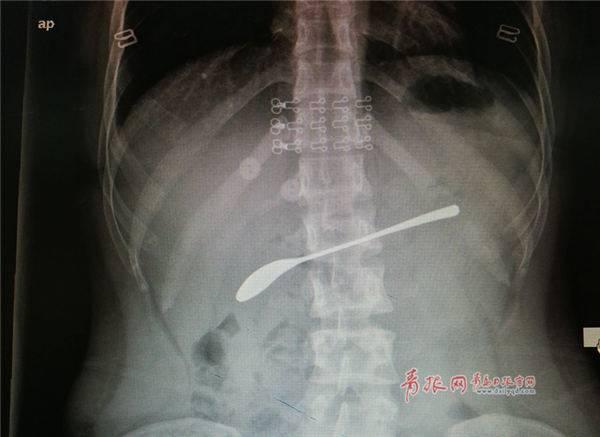

9月6日山东即墨区人民医院来了一名年轻女患者,她醉酒后误吞十几厘米的不锈钢汤勺,自己却浑然不知,直到腹痛难忍就医时才发现。

据医生跟患者沟通了解到,这个女孩前一晚喝酒的时候,嘴里含着一个勺子。而酒醉后的她在无意识的情况下,把这个15公分的勺子吞咽了下去!

勺子本身为不锈钢材质,在胃液的浸透下变得很滑,难以取出。但如果汤勺不及时取出,将有可能发生急性腹膜炎,进而带来生命危险。

据大夫范光学介绍,吞下钢勺的是一位二十多岁的女士,当天处于醉酒状态,不知道怎么回事就把勺子吞下了。“在胃镜下把勺子取出还是有一定难度的,首先勺子长度超过十厘米,再者它本身比较光滑,不是很好操作,既不好套住,套住之后往外拉也不好拉,很容易卡住。”范光学说,经过一番探索后,才终于缓慢地把钢勺取出,排除了险情。